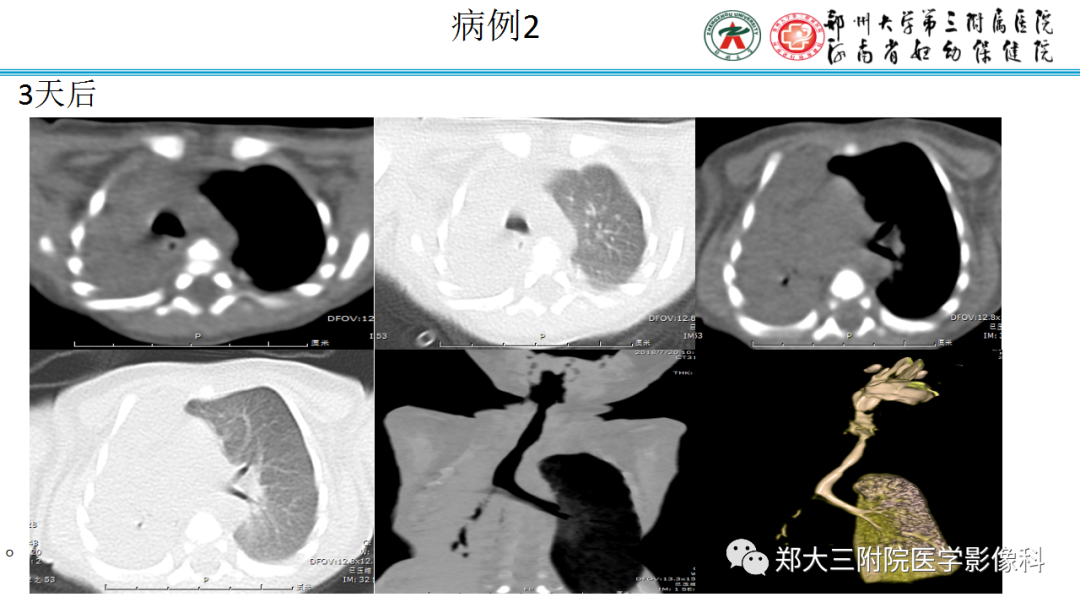

纵隔大细胞神经内分泌癌1例CT影像

纵隔大细胞神经内分泌癌1例CT影像  张力性纵隔气肿影像表现及严重度分级